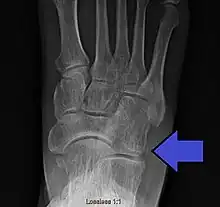

Avulsion fracture of the right cuboid bone of the foot

A cuboid fracture is a fracture of the cuboid bone of the foot. Diagnosis is by X-ray imaging, magnetic resonance imaging, or bone scan.[1] Treatment may be conservative or involve surgery, depending on the type of fracture.[1] They are rare.[1]

If the cuboid bone is broken, then it is common for other bones in the foot to be broken or dislocated as well.[2] Cuboid fractures are associated with Lisfranc injuries.[2]